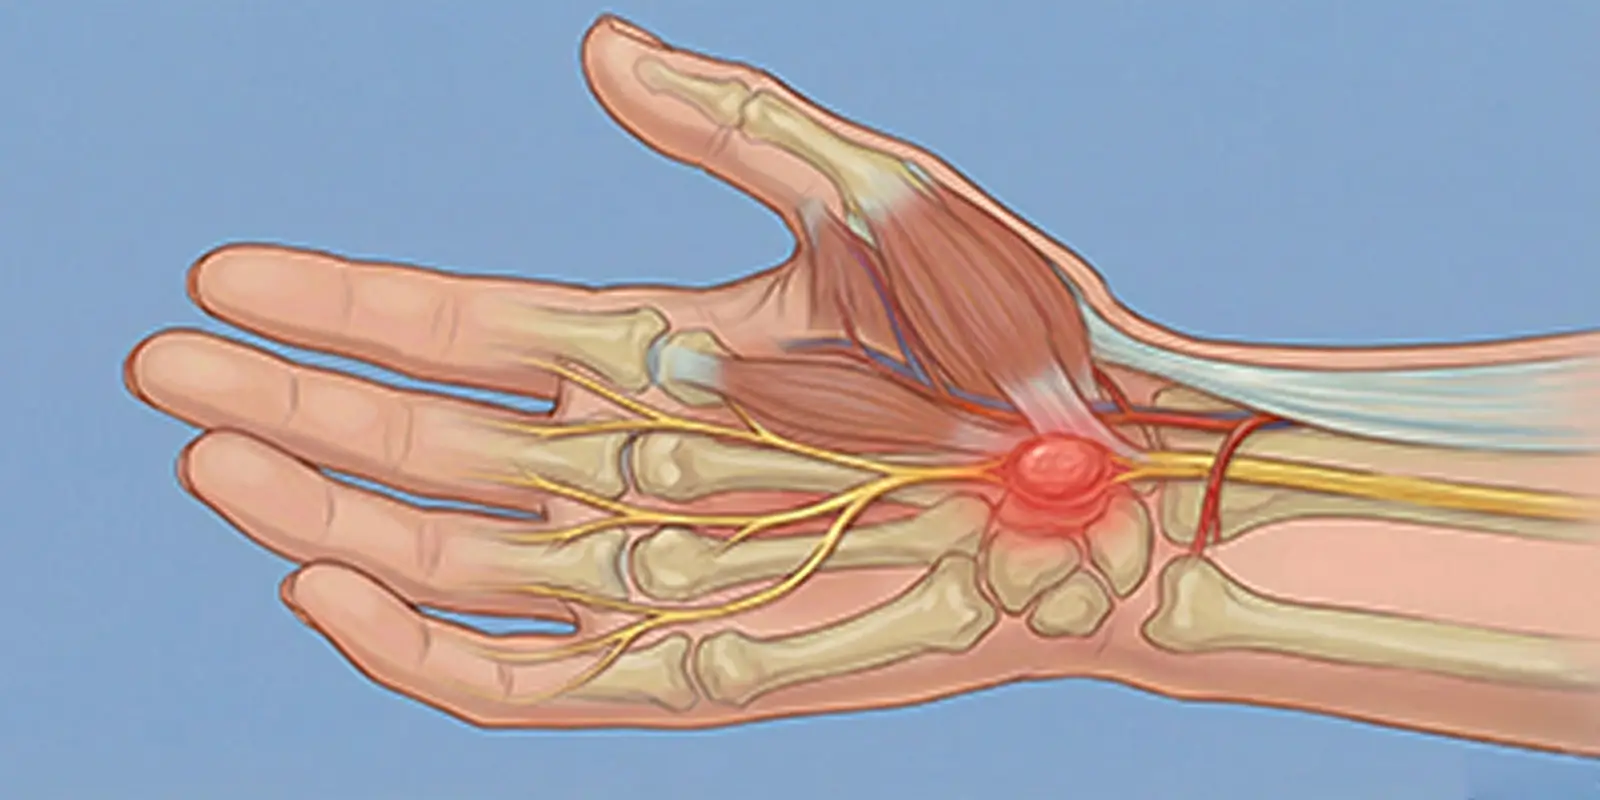

Schwannom, sinirleri saran Schwann hücrelerinden gelişen iyi huylu sinir kılıfı tümörüdür. Nedenleri, belirtileri, tanı ve tedavi yöntemleri.